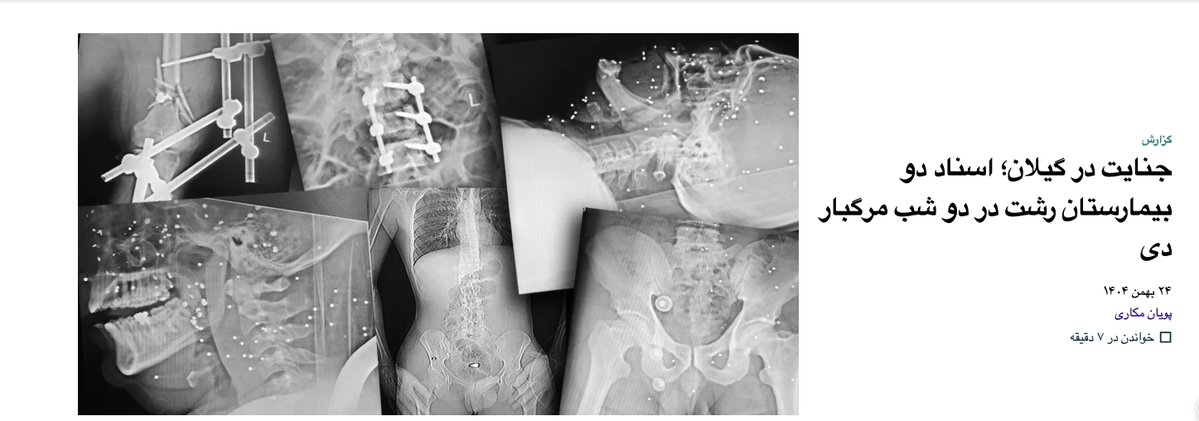

اسناد داخلی بیمارستان‌های رشت از سرکوب معترضان چه می‌گویند؟ گزارش تحقیقی من از سه شب مرگبار در گیلان؛ با تصاویر رادیوگرافی و پرونده‌های پزشکی که برای اولین‌بار منتشر می‌شوند. #اعتراضات_سراسری #IranMassacre ایران وایر iranwire.com/fa/features/14…

اسناد داخلی بیمارستان‌های رشت از سرکوب معترضان چه می‌گویند؟

گزارش تحقیقی من از سه شب مرگبار در گیلان؛ با تصاویر رادیوگرافی و پرونده‌های پزشکی که برای اولین‌بار منتشر می‌شوند.